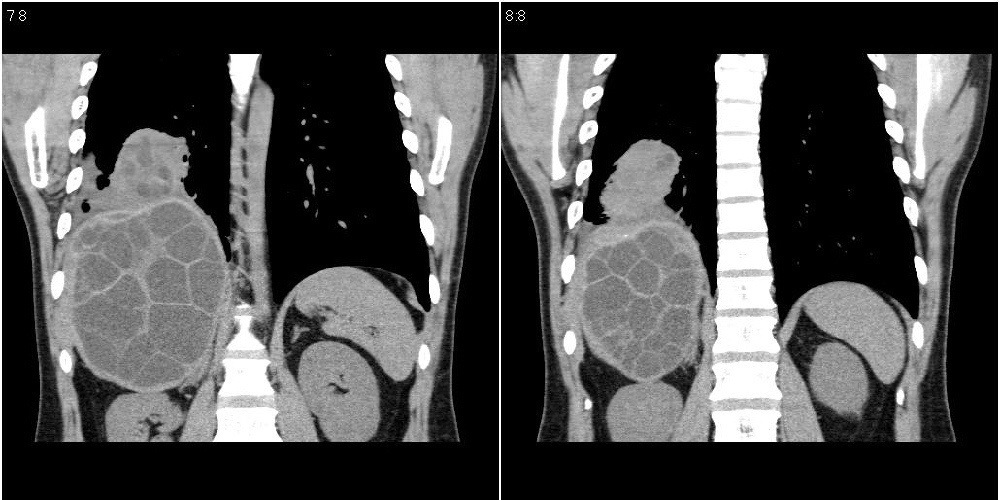

该患者70岁男性,手术后10年,现复查。2008年6月份本人曾经发过一极其类似的病例,只是部位略有差异。

多囊肝

肝脏多房性包虫囊肿

水上浮莲征,肝包虫囊肿。

肝脏及右侧胸腔包虫病。

大囊套小囊!肝脏多房性包虫囊肿